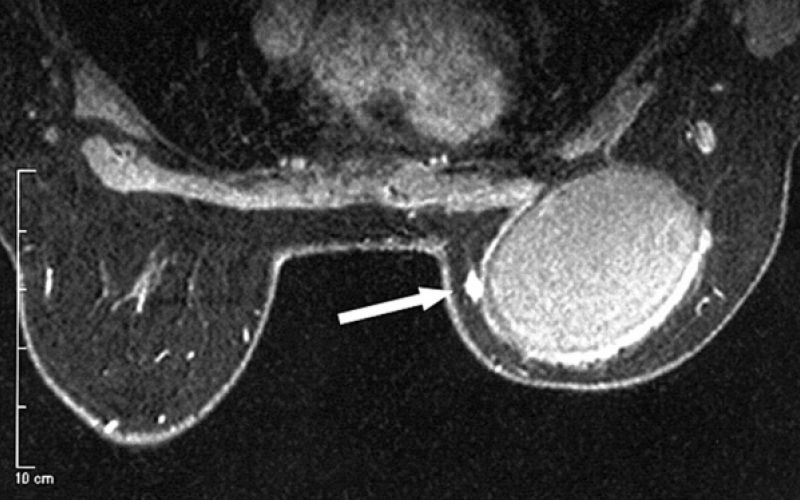

Zaradi prsnih vsadkov paničen strah pred rakom

Francoski nacionalni inštitut za rakave bolezni je ugotovil, da obstaja očitna povezava med redko obliko raka in določenimi vrstami prsnih vsadkov. Inštitut je ob tem ocenil, da ni potrebe po umiku vsadkov, ker so tovrstni zapleti zelo redki.